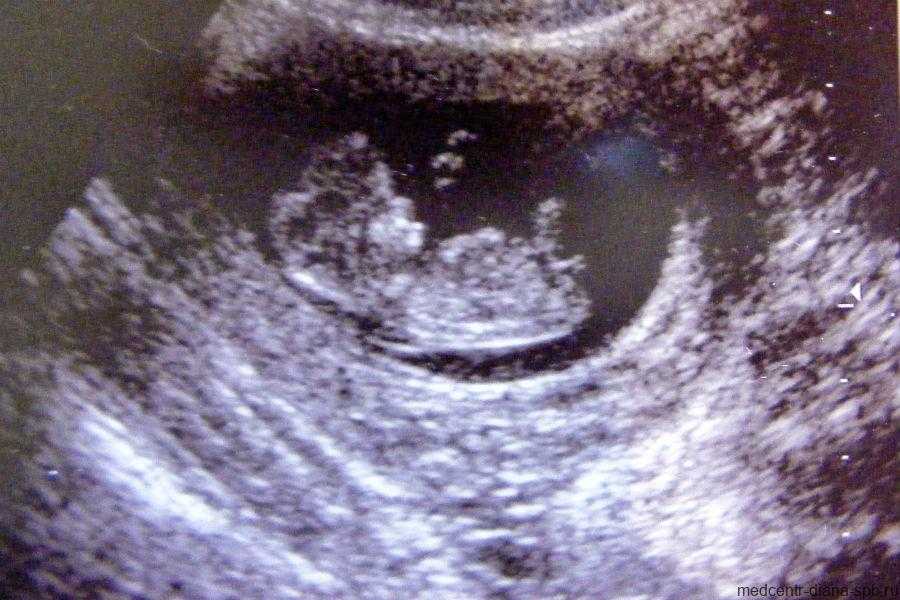

Фото УЗИ ребенка на 10 неделе беременности

На десятой акушерской неделе завершается закладка крупных внутренних органов. Вес малыша составляет уже 5 грамм. Хрящевая ткань при этом начинает уплотняться, превращаясь в костные структуры.

На фото УЗИ уже хорошо видны ручки и ножки малыша. Его голова несоизмеримо больше остального тела, а лобная часть явно выступает вперед. Пугаться этой особенности не стоит – это норма. Также на снимке можно отчетливо различить губы, нос и уши. Проводя ультразвуковое исследование, врач прослушивает сердцебиение, видит первые слабые движения конечностей. Также специалист может осмотреть строение позвоночника.